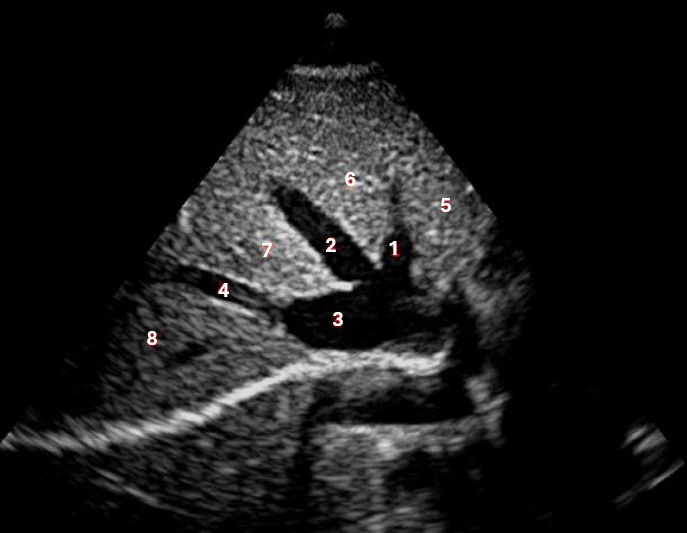

Which of the following structures is labeled number #1?

Left hepatic vein

Which of the following structures is labeled #2?

Middle hepatic vein

Which of the following structures is labeled #3?

IVC

Which of the following structures is labeled #6?

Medial left lobe

Which of the following structures is labeled #4?

Right hepatic vein

Which structure/vessel is indicated by #5?

Lateral left lobe

Which of the following structures is labeled #8?

Posterior right lobe